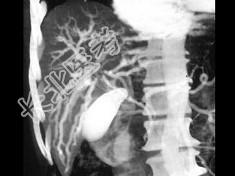

- 单项选择题患者中年,男性, 黄疸,ERCP术后, 三维图像如图,最可能的诊断为 ( )

A、胰腺癌

B、末梢胆管狭窄

C、胆管癌

D、肝门区肝癌

E、十二指肠癌